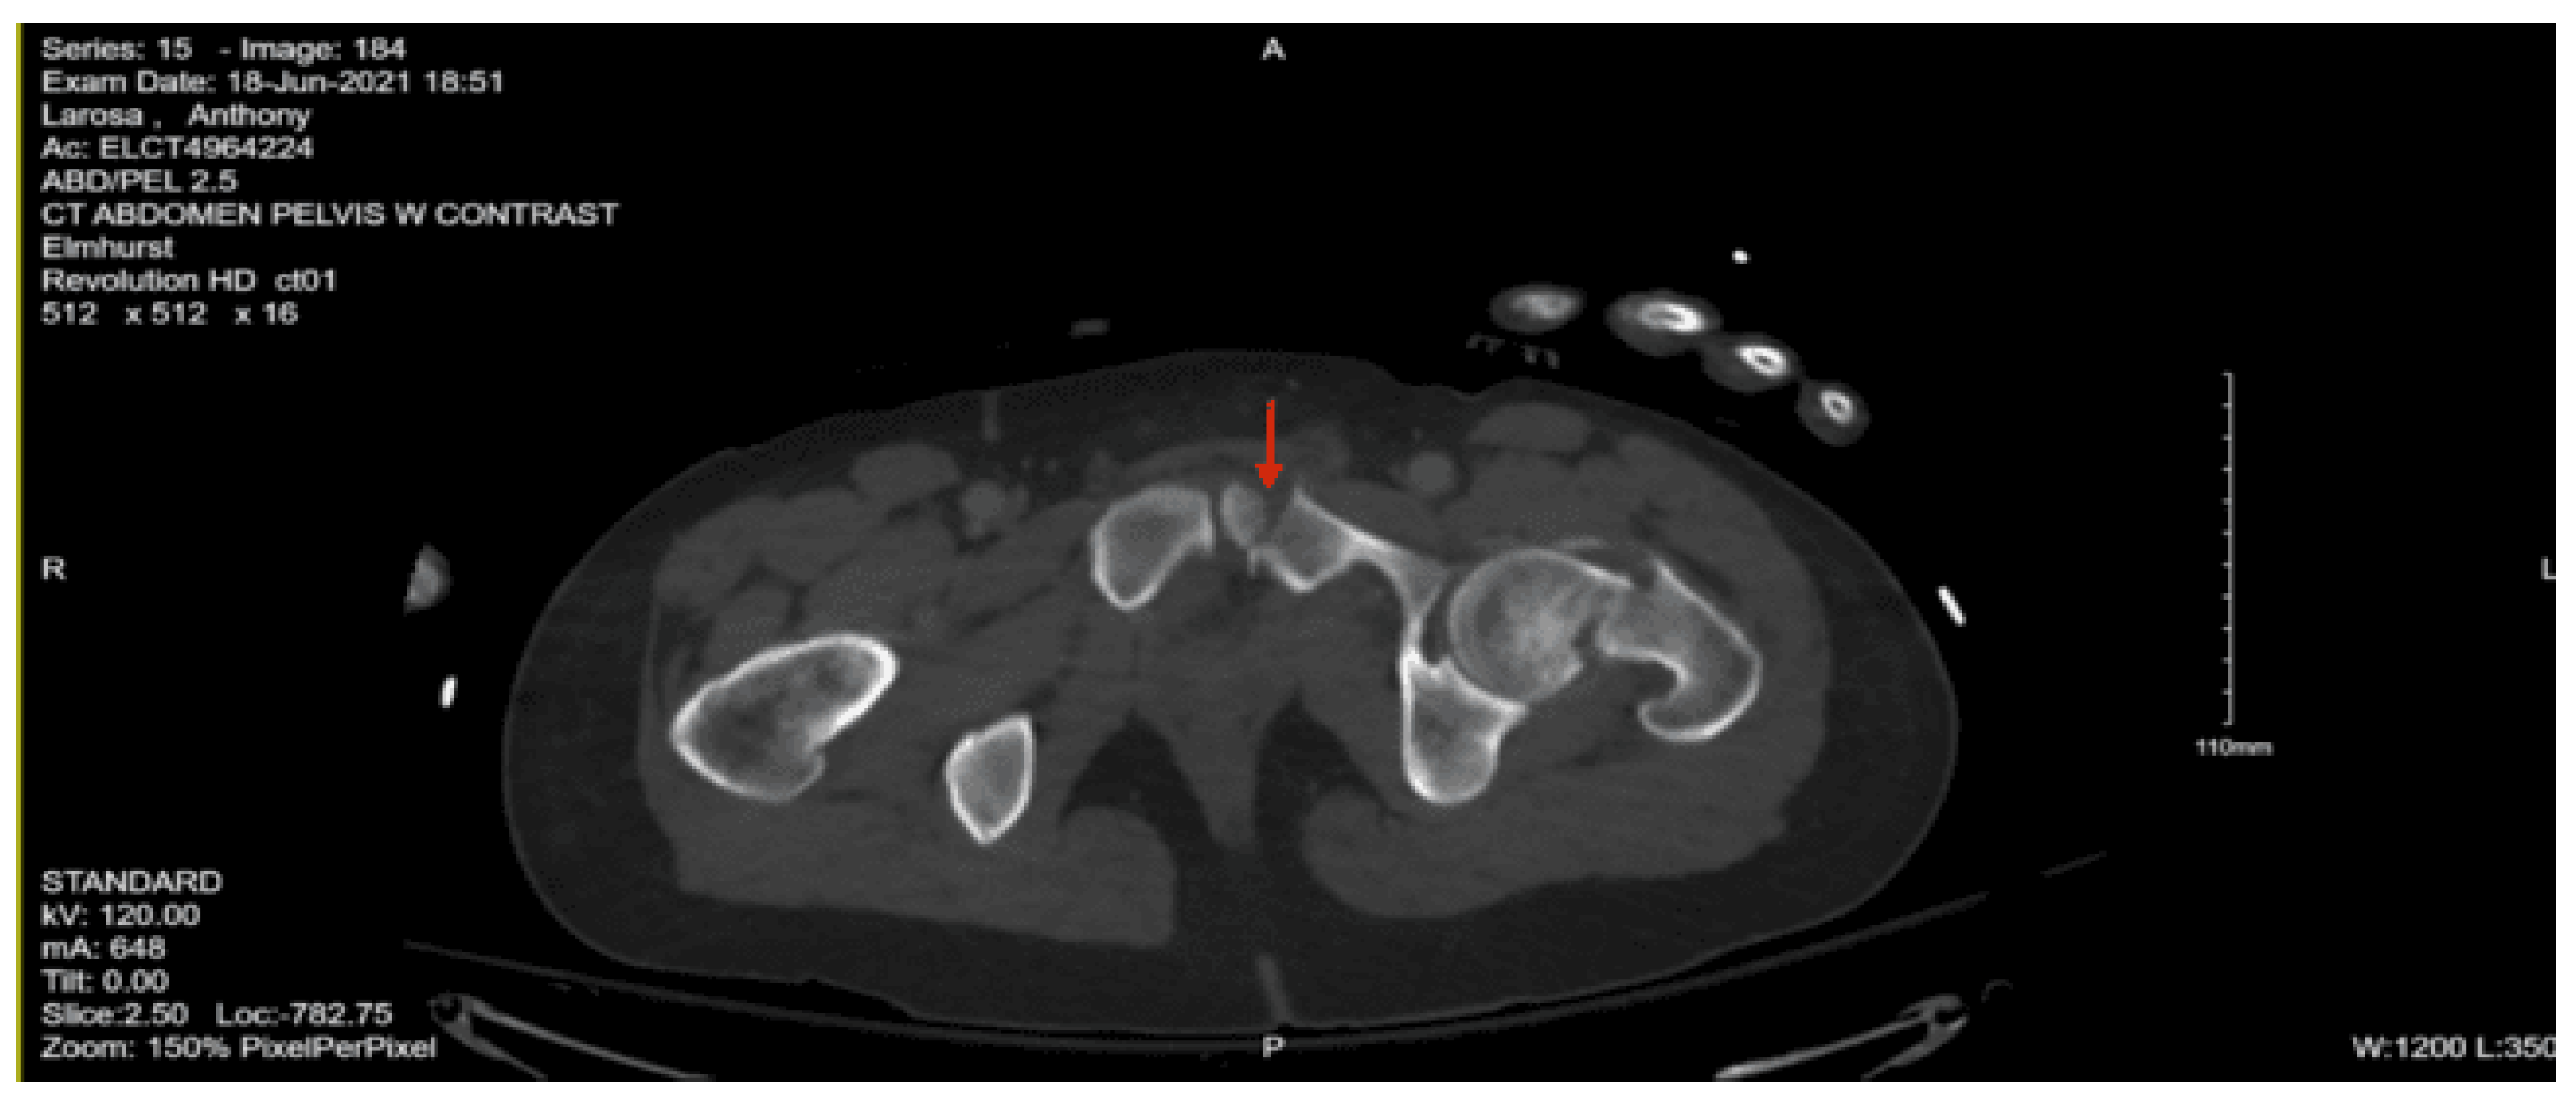

Imaging as shown in Figure 1, Figure 2 and Figure 3:

CT abdomen/pelvis with contrast: Acute fractures are seen involving the right superior pubic ramus and left inferior pubic ramus. An acute comminuted avulsed fracture of the left sacral wing in the superior and midportion is demonstrated. No definitive acute traumatic visceral abnormalities were found throughout the abdomen and pelvis.

DX: Denis zone II left sacral alar fx involving S1 foramina. AOSpine B3: NX, M3